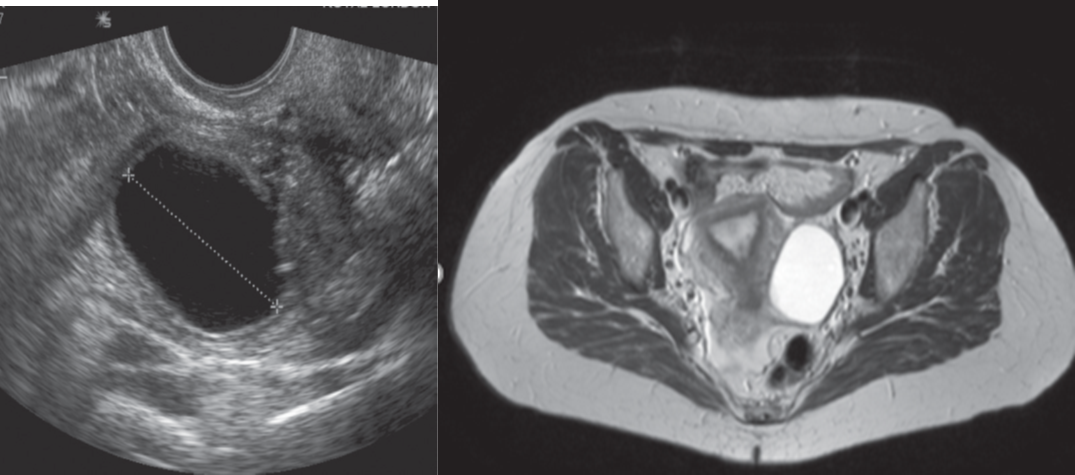

Sometimes a follicle or corpus luteum persists as a follicular or corpus luteum cyst, both of which are easily recognized by ultrasound, CT or MRI.

Follicular cysts are mostly asymptomatic and regress spontaneously.

Corpus luteum cysts are most often seen in the first trimester of pregnancy; they usually resolve, but may rupture or twist.